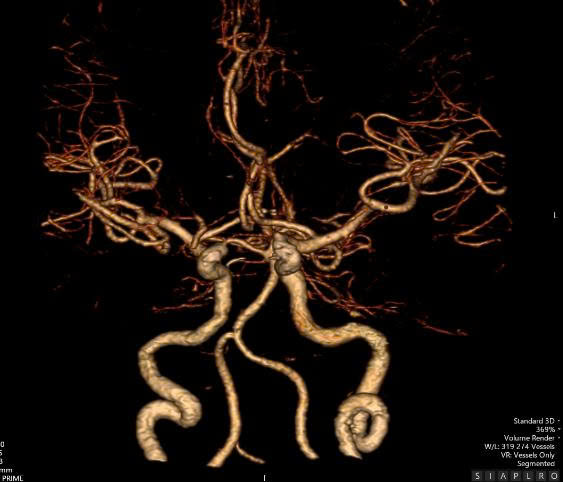

Ngay khi tiêm thuốc, bệnh nhân đã giảm chóng mặt nhanh chóng, giảm thất điều và bệnh nhân có thể giữ thăng bằng khi ngồi, cũng như đi lại. Anh B. có thể tự đi lại và vận động bình thường, không ghi nhận hẹp hay tắc mạch máu lớn trên phim CT mạch máu não. Đây là minh chứng rõ rệt cho hiệu quả của việc cấp cứu đột quỵ đúng thời điểm, vì “thời gian là não”.

Hình chụp CTA không ghi nhận tắc mạch máu lớn